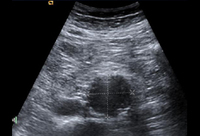

Ultrasound of a 3.8 cm x 4.2 cm AAA

University of Michigan, specifically the cases of Dr Upchurch reflecting the Departments of Vascular Surgery and Radiology